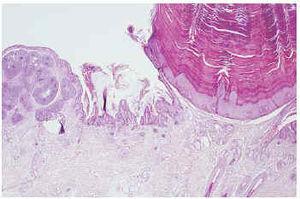

Fig. 5A y B.--Nevo sebáceo asociado a siringocistadenoma papilífero.

Las cuatro entidades histológicas más frecuentemente relacionadas con el nevo fueron la verruga vírica en 15 pacientes (4,09 %), siringocistadenoma papilífero en 12 pacientes (3,27 %), tricoblastoma en 8 pacientes (2,18 %) y carcinoma basocelular en 7 pacientes (1,91 %). En 12 casos se observaron lesiones múltiples que se desarrollaban sobre un mismo nevo. Se identificaron hasta tres lesiones diferentes asociadas simultáneamente al nevo sebáceo (tabla 1). La mayoría de las lesiones asociadas se localizaron en el cuero cabelludo (60,52 %), región frontal (21,05 %) y cara (13,15 %). El tipo histológico y la distribución de las lesiones asociadas según edad se reflejan en tablas 2 y 3.

Todas las series hasta ahora publicadas3-6 coinciden en señalar el siringocistadenoma papilífero como la lesión tumoral benigna más frecuentemente asociada con nevo sebáceo. Probablemente su aparición se deba a que las glándulas apocrinas heterotópicas localizadas en las zonas más profundas del nevo tiendan a sufrir dilatación y quistificación, abriéndose al exterior por ulceración de la superficie epidérmica. Este último cambio induce a la extirpación quirúrgica de la lesión. En nuestra serie, sin embargo, el siringocistadenoma papilífero es la segunda lesión en frecuencia que se asocia al nevo sebáceo, tras la verruga vírica. También en la serie de Jaqueti et al7 la verruga vírica es la lesión que más se asocia al nevo (14,8 %), así como el tricoblastoma (7,7 %) y el siringocistadenoma (6,4 %). En la serie de Cribier et al6 se describen 16 tricolemomas y 14 verrugas víricas que, en conjunto, suman tantos casos como los de siringocistadenoma asociado a nevo sebáceo, aunque el autor no destaca esta circunstancia.